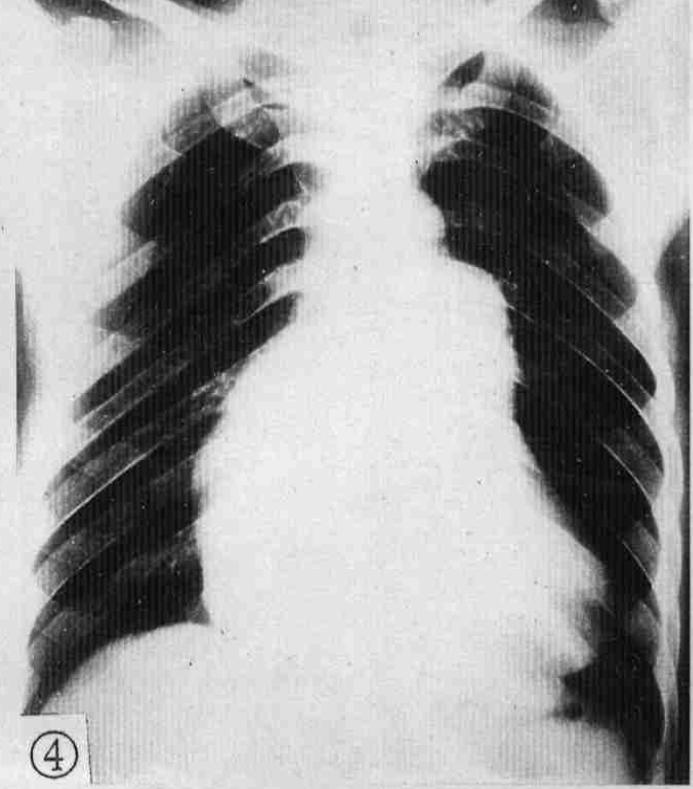

2.右心室增大

常见于心脏瓣膜病二尖瓣狭窄、肺源性心脏病、肺动脉狭窄、肺动脉高压、先天性心脏病如法络四联症等。见图2。

图2 正位片见左心缘向左侧膨隆,心尖上翘,主动脉结缩小